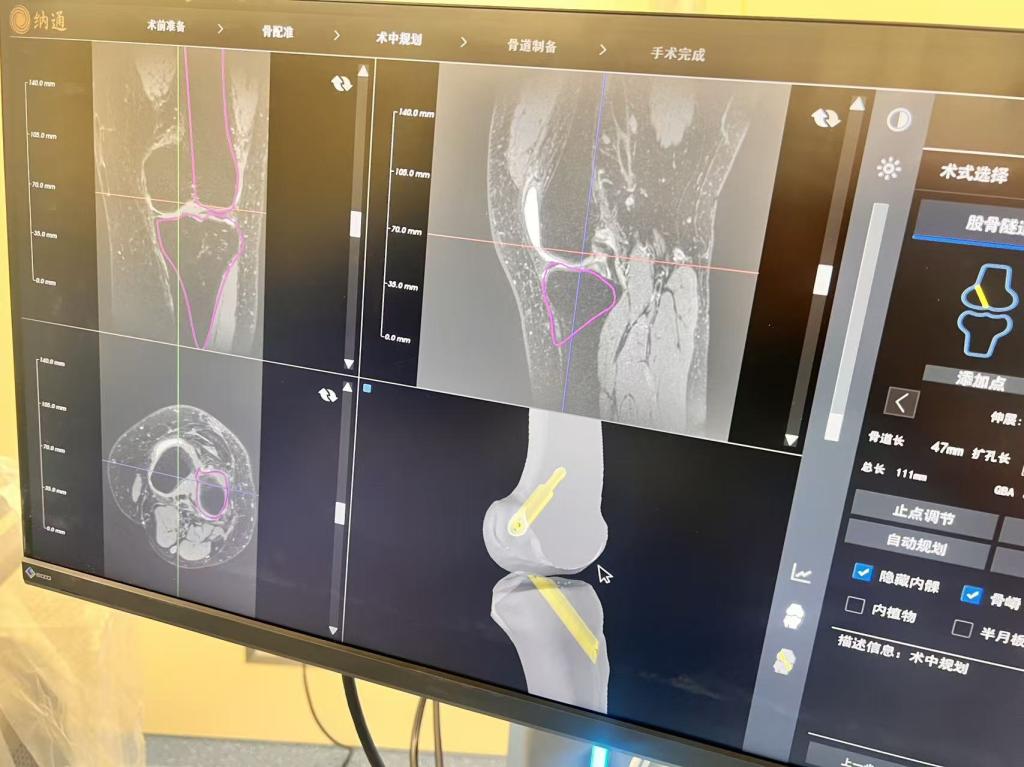

11月24日,我院骨科运动创伤与关节镜外科成功完成安徽省首例机器人辅助下前交叉韧带重建手术。该手术标志着我院运动损伤诊疗正式迈入智能化、精准化新阶段,展现了医院在运动医学领域持续创新的技术实力。

本次接受手术的是一位19岁女性患者,因不慎摔伤导致前交叉韧带断裂,并伴有膝关节多发韧带松弛,传统手术难度及风险较高。经科室徐洪港主任团队全面评估,决定为其施行机器人辅助手术。术中,团队借助多模态影像融合技术构建膝关节精准3D模型,在机器人亚毫米级精度引导下完成骨道制备,并同步进行运动学与动力学评估,确保重建韧带符合患者个体化生物力学特征。手术过程顺利,出血少,患者术后反应良好。